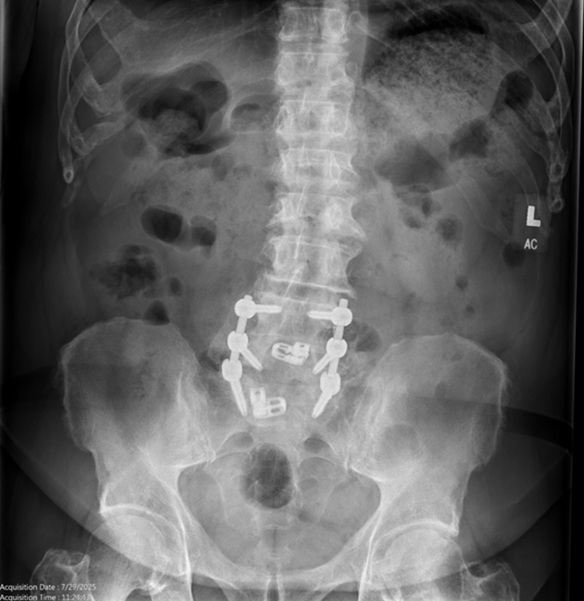

Figures 6 and 7. AP and Lateral of the Lumbar spine demonstrating previous lumbo-sacral fusion.

Pre-op Spine Images

Figure 5.

Figure 6.